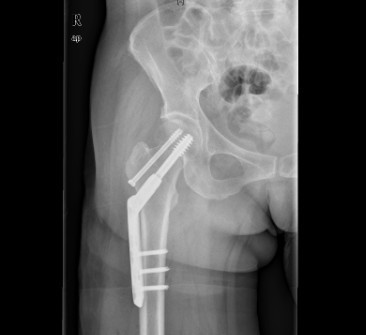

患者女,61岁,因“摔伤致右髋关节疼痛、活动受限9小时”入院。患者于入院前9小时行走时不慎摔倒,右侧肢体着地,当即感右髋关节及右大腿上段疼痛,活动受限,不能自行站立,受伤时及伤后无昏迷,无恶心、呕吐,无心累、气促,无腰痛及肉眼血尿。因休息后无缓解,急诊到当地医院行骨盆平片提示“右股骨颈骨折”,未做任何治疗,患者为求进一步治疗,遂急诊来我院,急诊以“右股骨颈骨折”收入住院。

查体:右髋关节、右大腿皮肤完整性好,右下肢轻度外旋。右腹股沟中点压痛明显,右股骨无明显压痛,未扪及明显骨擦感。右髋关节主被动活动受限。右下肢较左下肢短缩1cm。 辅查:院外X片右股骨颈骨折。

诊断:1、右股骨颈骨折(Garden III);2、骨质疏松症 治疗:择期手术